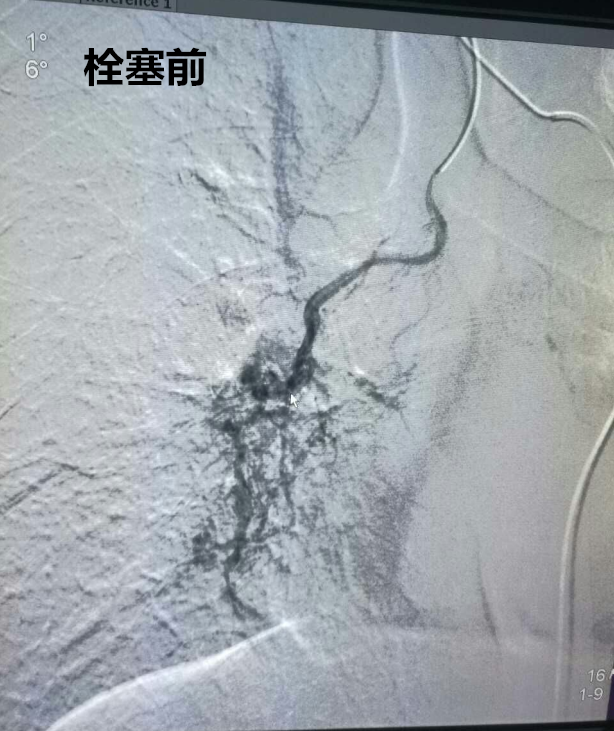

近日,我院影像科为一名患有双肺结核并伴有咯血的患者成功实行支气管动脉栓塞术,手术顺利,术后患者未再出现咯血。

栓塞前.png

629日,患者术前一切准备就绪,于下午2时被推入介入手术室,在局麻下,先行DSA检查,确定患者左支气管动脉、右支气管动脉及左侧内乳动脉共有3支血管出血,然后经造影导管送入微导管,进一步分别超选3支动脉的出血动脉分支,并用适量栓塞微粒球及PVA颗粒分别对出血动脉进行栓塞,然后行DSA检查确定栓塞效果满意后撤出微导管。约1.5个小时,手术顺利完成。术后患者未再出现咯血,无明显不良反应,恢复良好,两天后出院。